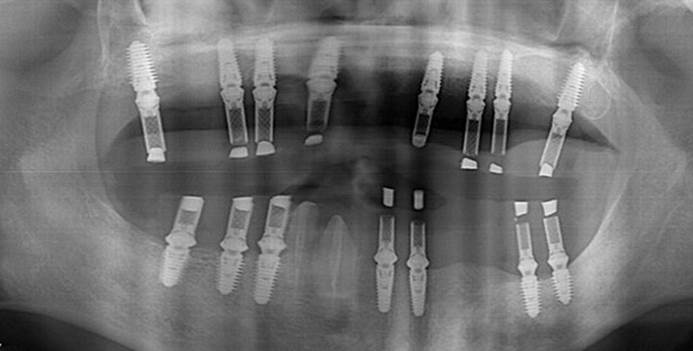

Clinical case: Full-mouth implants for mandibular & maxilla - restored using mixed prostheses

- Courtesy of Dr. Hyun Jun Kim, Korea -

Keywords

AnyRidge, full-mouth implants, mandibular, maxilla, edentulous, full mouth rehabilitation, Octa abutment, long-term clinical case, biological stability, Dr. Hyung Jun Kim

Products:

AnyRidge implant system